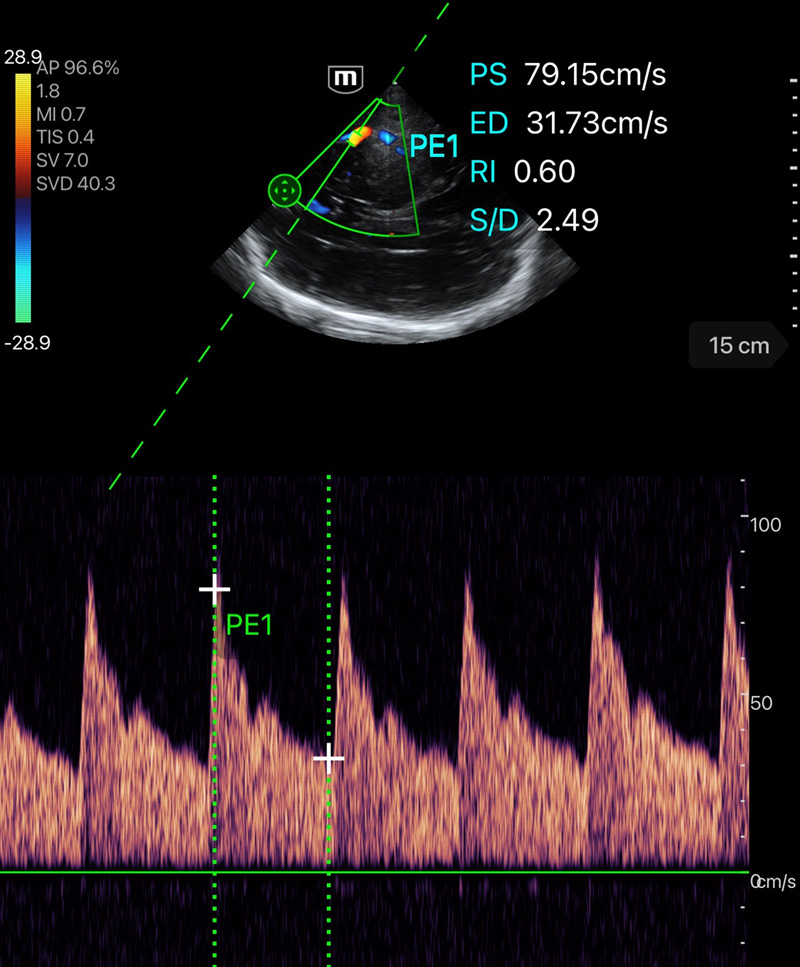

Immagini cliniche

Doppler della velocitأ tissutale

Immagini cliniche

Doppler della velocitأ tissutale